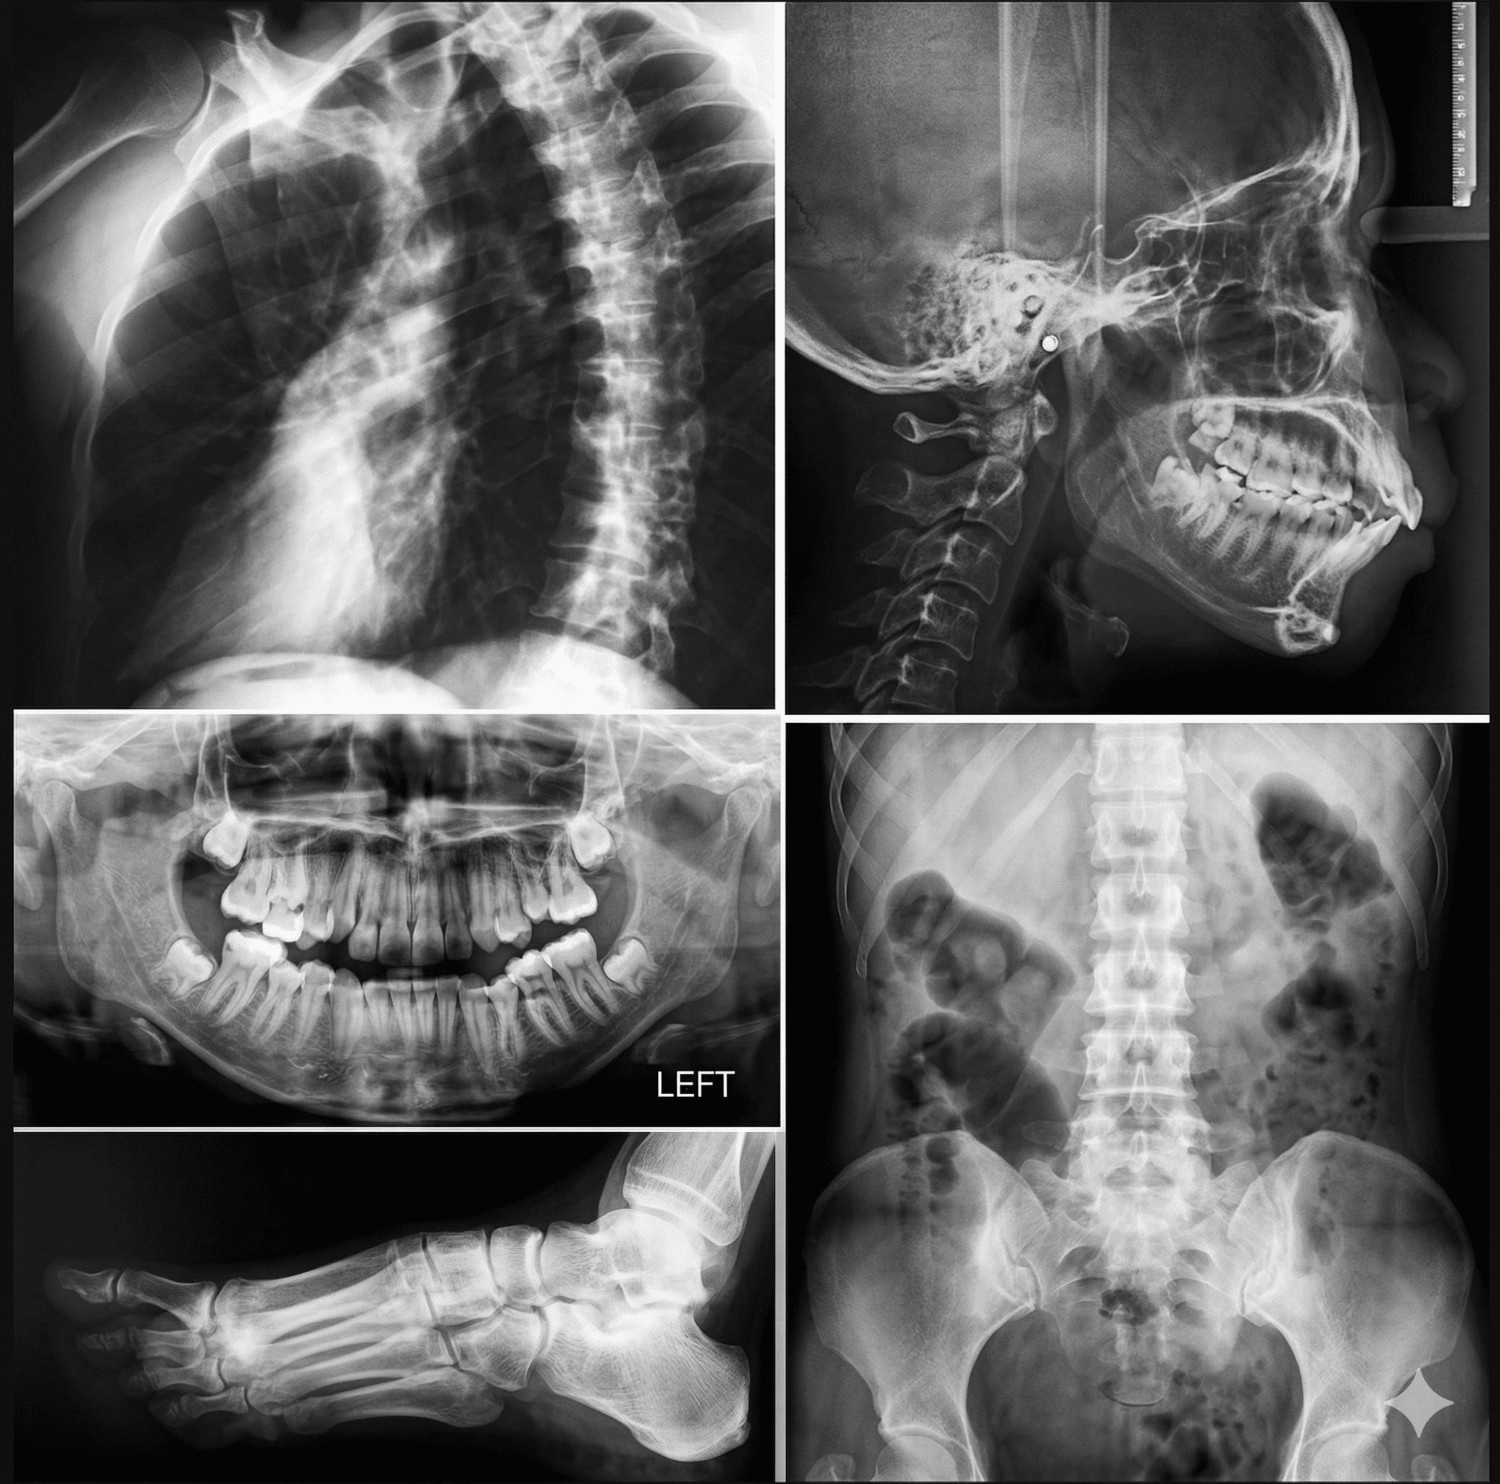

X-Ray

We offer advanced X-ray imaging services, a non-invasive and rapid diagnostic technique that uses low-dose ionizing radiation to visualize internal structures. This modality is highly effective for assessing bones, fractures, infections, and various soft tissue conditions. All examinations are conducted by experienced technologists, ensuring high-quality image acquisition. The resulting images clearly differentiate structures, with dense tissues such as bones appearing white, and softer tissues appearing in varying shades of grey, enabling accurate and reliable diagnosis.

Chest X-ray Bone X-ray Dental X-ray Mammography Abdominal/KUB X-ray